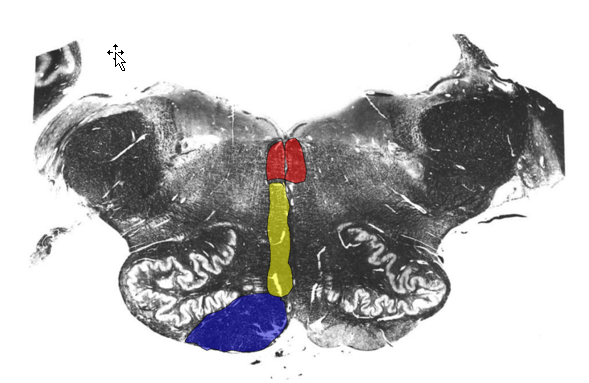

List the three prominent features found at the midolivary level

Prominent Features

Inferior olivary complex

Hypoglossal nerve

exits preolivary sulcus

Vagus nerve

exits postolivary sulcus

Describe the Structures found @ Midolivary Level

Inferior Olivary Complex:

Constituents:

Principle Olivary Nucleus

Function:

Control of planned or skilled voluntary movement

predominantly cortical (and subcortical) afferents

Medial/Dorsal Accessory Olive

Stereotyped Movement

Receives predominantly spinal afferents

inferior cerebellar peduncle (olivocerebellar tract)

inferior olive → cerebellum (contralaterally)

Reciprocally connected